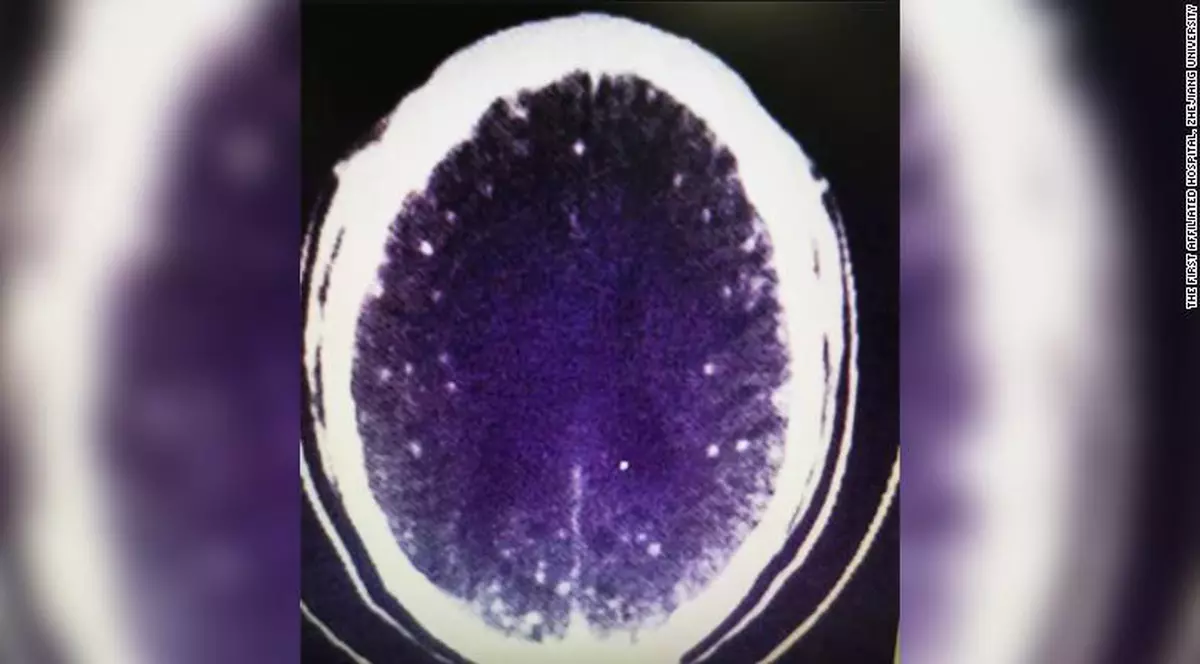

Studiul, publicat în revista Biological Psychiatry, a implicat șaptesprezece pacienți cu tulburare depresivă majoră sau depresie cauzată de boala Parkinson și 20 de voluntari sănătoși. Participanților li s-a făcut o scanare PET pentru a afla cât de multă serotonină se leagă de anumiți receptori din creier.

Li s-a administrat apoi o doză de amfetamină, care stimulează eliberarea serotoninei și au fost scanați din nou. Un răspuns redus la serotonina a fost observat la pacienții cu depresie, au descoperit cercetătorii.